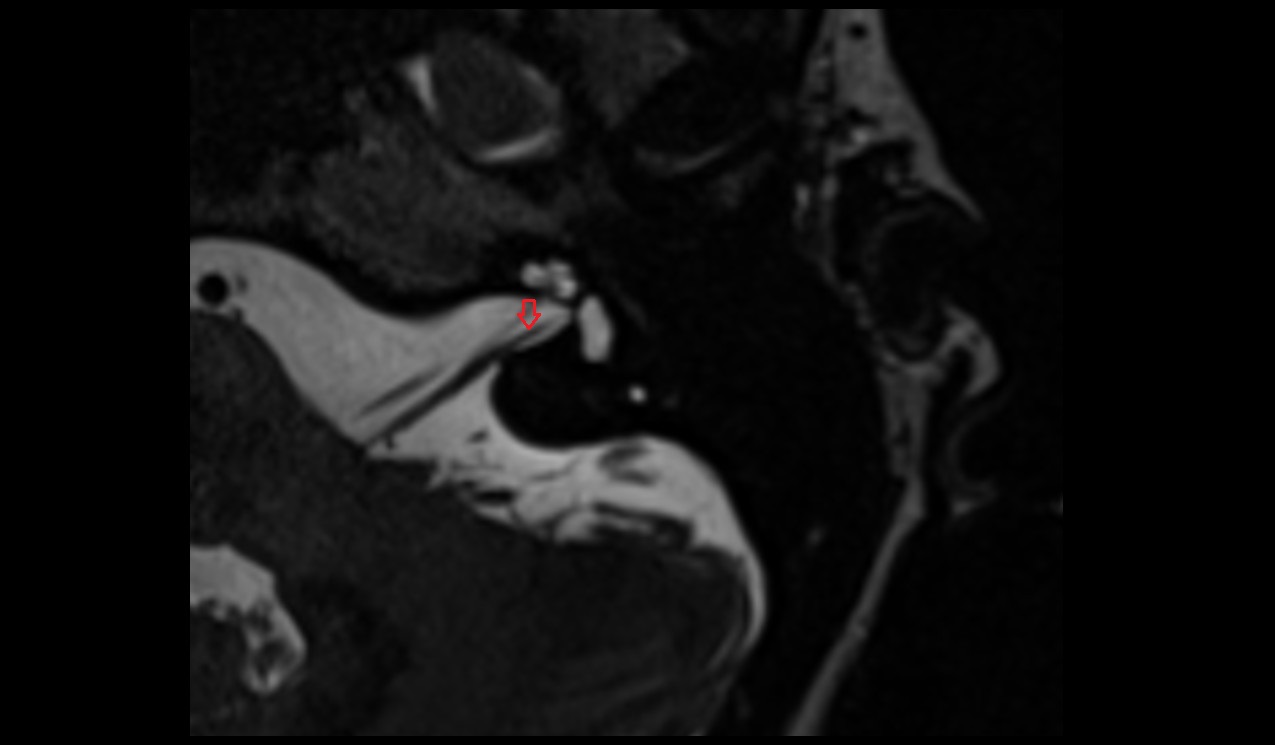

- Temporomandibular joint

- Articular disc of temporomandibular joint

- Articular eminence

- Mandibular condyle

- Mandibular fossa